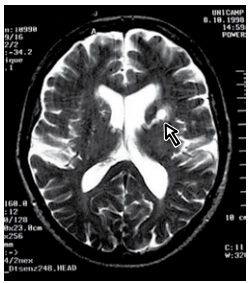

Um paciente de 75 anos com histórico de hipertensão e fibrilação atrial em uso de rivaroxabana (20 mg/dia) apresenta disartria súbita. A ecocardiografia transtorácica revelou dilatação moderada do átrio esquerdo e hipertrofia ventricular esquerda, mas sem trombos intracardíacos. O monitoramento contínuo não detectou fibrilação atrial adicional. A avaliação inicial com ressonância magnética encontra-se a seguir. Enunciado 4448958-1 (https://www.google.com/url?sa=i&url=https%3A%2F%2Fanatpat.unicamp. br%2Fradlacunaris1.html&psig=AOvVaw1FPStQZC4RupNqKV2_4rG7&u st=1734781327580000&source=images&cd=vfe&opi=89978449&ved=0CBQ QjRxqFwoTCNDSqJ-itooDFQAAAAAdAAAAABAE)

Com base no quadro clínico e nas diretrizes atuais, o próximo passo mais apropriado no manejo do paciente é: